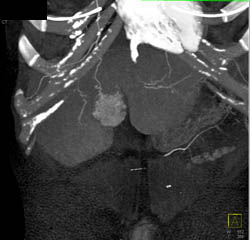

Hepatic Adenoma